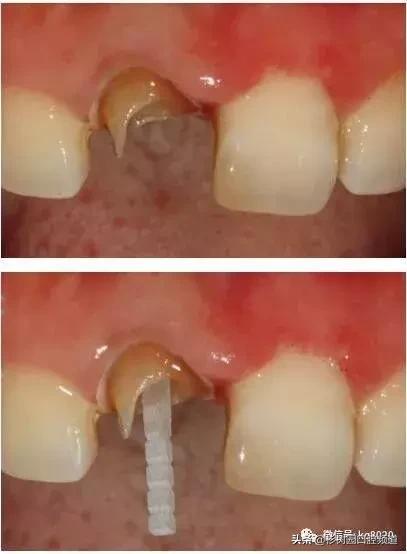

要尽可能的保存牙本质肩领,宽度应达到1.5mm—2.0mm以上。

如果剩余牙体组织很少,不要为了预备出牙本质肩领,而向龈下预备太多,破坏生物学宽度。

尽可能的多保存牙体组织,纤维桩预备也是同样如此。

但过于薄弱的牙体组织是应该去除的,书中给出的标准是牙体组织的厚度要超过1.0mm才能保留,否则决不姑息,一律磨掉。

如下图剩余的组织就过于薄弱,以后也是一个安全隐患。